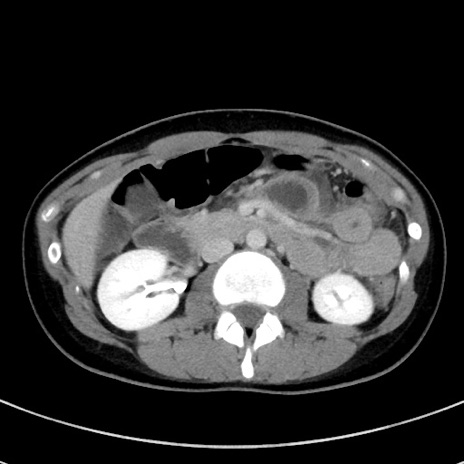

症例17(横断像)

【症例】20歳代女性

【主訴】嘔吐、下腹部痛

【現病歴】昨日夕食後に嘔吐し下腹部痛が出現。本日になっても嘔吐持続し改善しないため来院。

【身体所見】意識清明、BT 37.2℃、BP 108/67mmHg、腹部:平坦、やや硬、下腹部正中から右にかけて圧痛あり、反跳痛軽度あり、tapping pain(+)。

【データ】WBC 13600、CRP 14.94